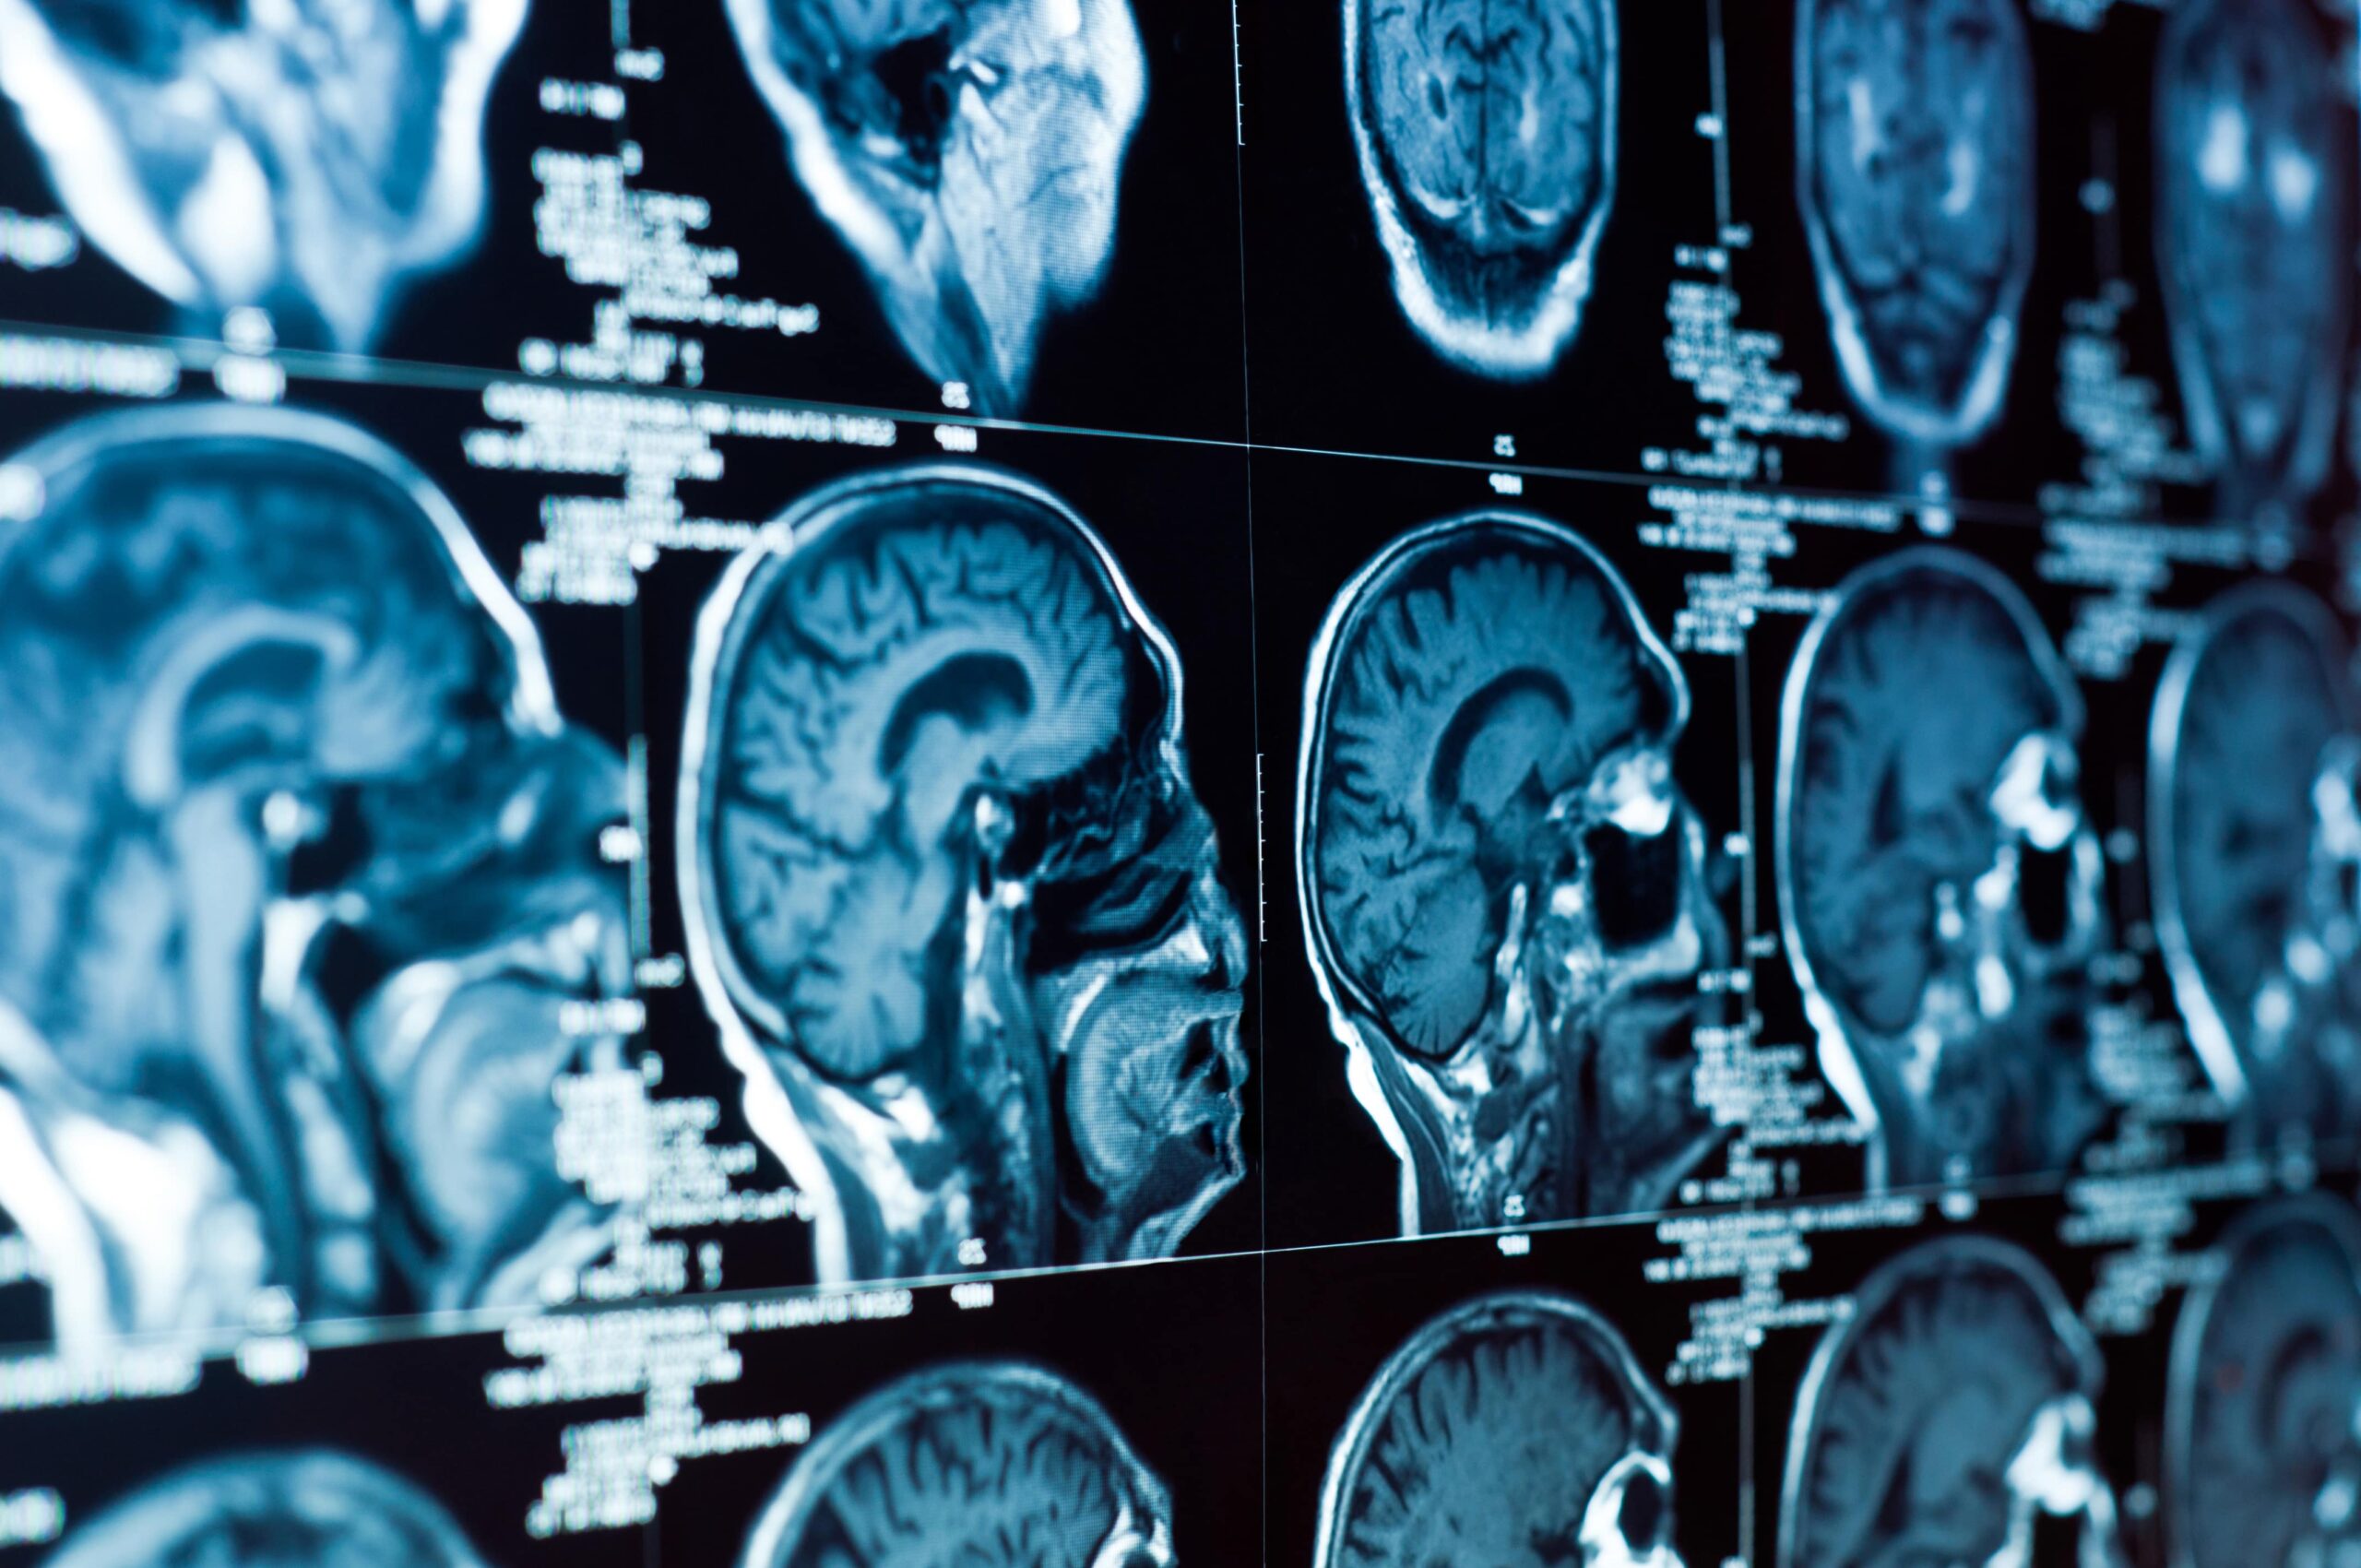

Recovering From A TBI After An Accident